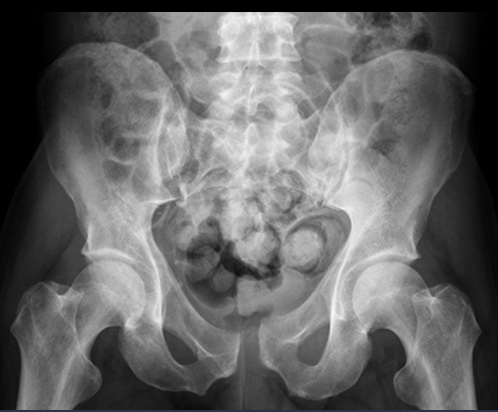

What is represented by 1 and 2 in the AP pelvic radiograph?

1. sacrum

a. ala

b. foraminae

2. sacroiliac joint

What is represented by 3 and 4 in the AP pelvic radiograph?

3. ilium

a. crest

b. ASIS

c. AIIS

4. ischium

a. spine

b. tuberosity

What is represented by 5 in the AP pelvic radiograph?

5. pubis

a. body

b. superior ramus

c. inferior ramus

d. symphysis

What is shown here?

Which age group is usually affected?

fracture of the superior and inferior pubic rami on the right-hand side

common in elderly patients through trips, low-energy falls

What condition is shown here?

diastasis of the pubic symphysis

this is where the pubic symphysis is wider than it should be